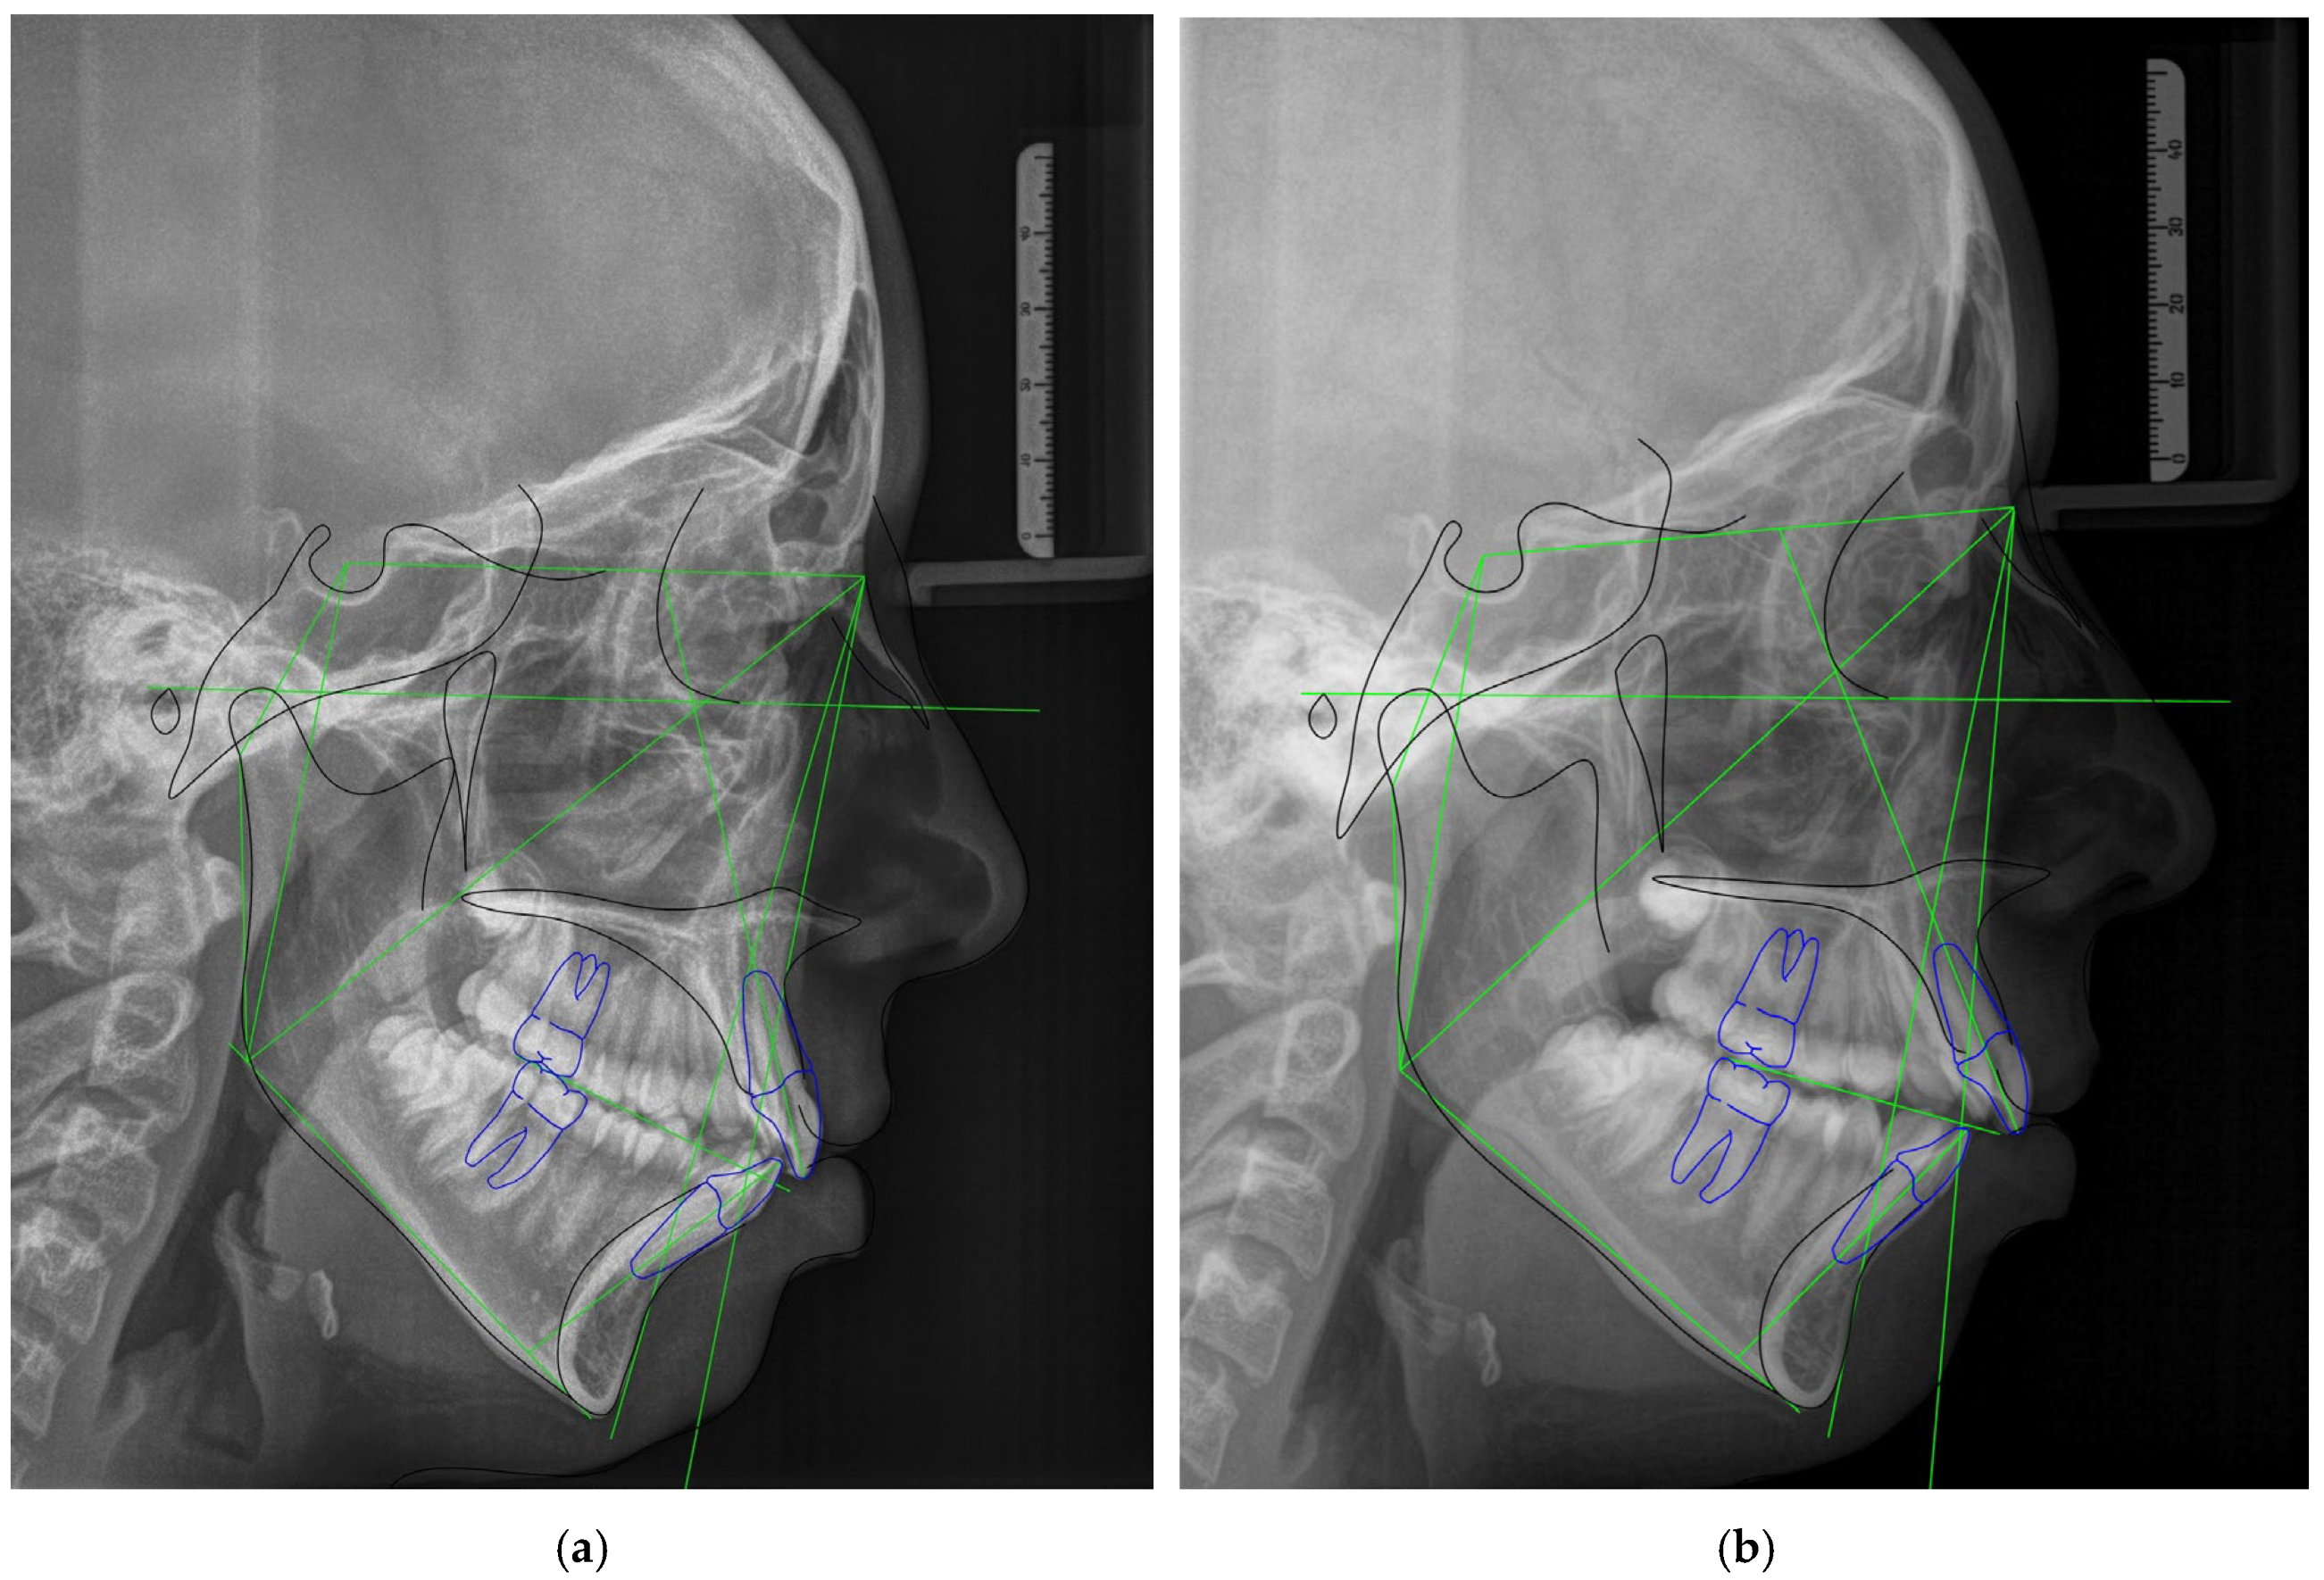

2.4. Radiologic Evaluation

- Park, J.H.; Lee, S.M.; Moon, D.N.; Lee, G.H. Clinical application of a maximum intercuspal position-centric relation occlusion conversion of a lateral cephalogram in the treatment of orthodontic patients. Am. J. Orthod. Dentofac. Orthop. Clin. Companion 2021, 1, 127–135. [Google Scholar] [CrossRef]